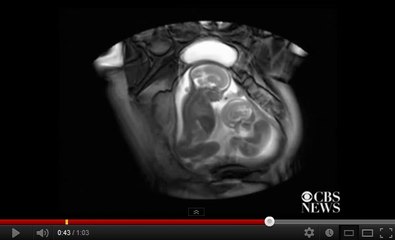

Ces deux jumeaux se battent pour gagner de la place dans l'utérus